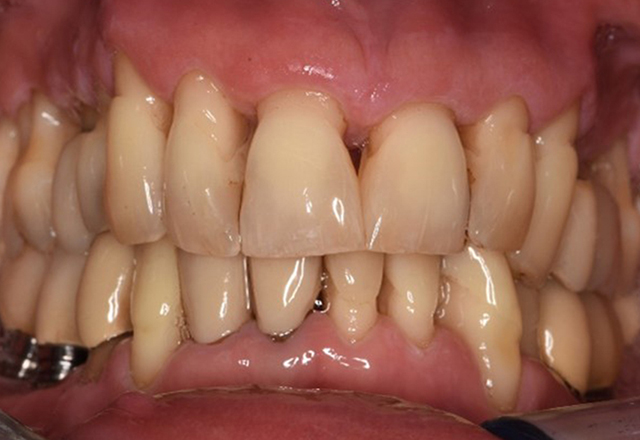

Die gesunde Patientin mit parodontaler Vorerkrankung

Die 68-jährige Patientin hat keine zahnmedizinisch relevanten allgemeingesundheitlichen Vorerkrankungen oder Medikation, auch aus dem Lebensstil ergibt sich kein besonderes Risiko. Die Patientin hat zwei Implantate (3. Quadrant, seit fünf Jahren) sowie eine parodontale Vorerkrankung (Parodontitis Stadium IV, Grad B) mit Zahnverlust. Derzeit zeigen sich stabile parodontale Verhältnisse. Für die Prophylaxesitzung ergeben sich vier Empfehlungen in den Bereichen Anamnese/Befund, Motivation/Instruktion, der Wahl der geeigneten Instrumente und für Resümee/Folgetermin. mehr Infos